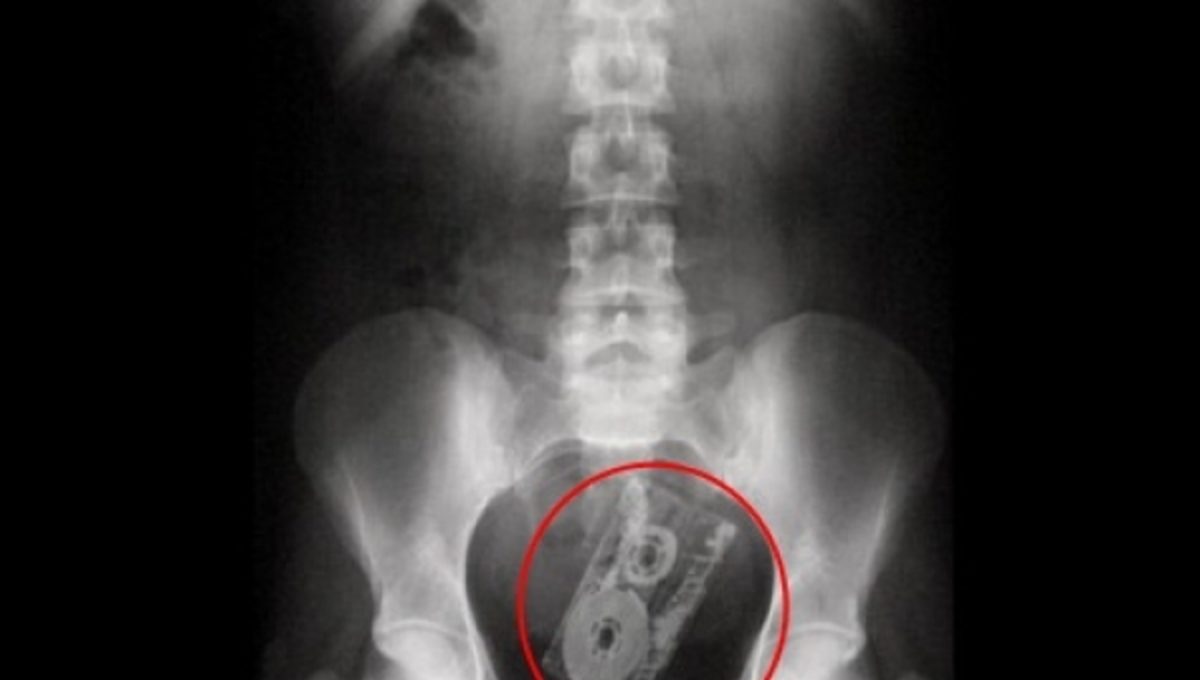

Ό,τι μπορεί να σκεφτεί ο ανθρώπινος νους αφαιρούν οι γιατροί μέσα από τα στομάχια των ασθενών τους. Κέρματα πιρούνια, κομμάτια από πλακάκια ακόμη και ...κλειδιά αυτοκινήτου. Όταν η κατάσταση φτάνει στο απροχώρητο και ο πόνος από την κοιλιά δεν υποχωρεί με τίποτα τότε οι πάσχοντες απευθύνονται σε κάποιο γιατρό και στις επίμονες ερωτήσεις τους αν κατά λάθος κατάπιαν κάτι το αρνούνται.. μέχρι να γίνει η πρώτη ακτινογραφία που θα αποκαλύψει τα πάντα. Δείτε ορισμένες ακτινογραφίες με τα πιο περίεργα αντικείμενα που ανακάλυψαν οι γιατροί μέσα σε σώματα ασθενών.

Αυτή η ακτινογραφία απεικονίζει το στομάχι ενός αγοριού το οποίο κατάπινε μαγνητικά κομμάτια από ένα τετράγωνο παιχνίδι ένα τη κάθε φορά. Όταν έφτασαν στο στομάχι του, τα κομμάτια κατάφεραν να επανασυνδεθούν.